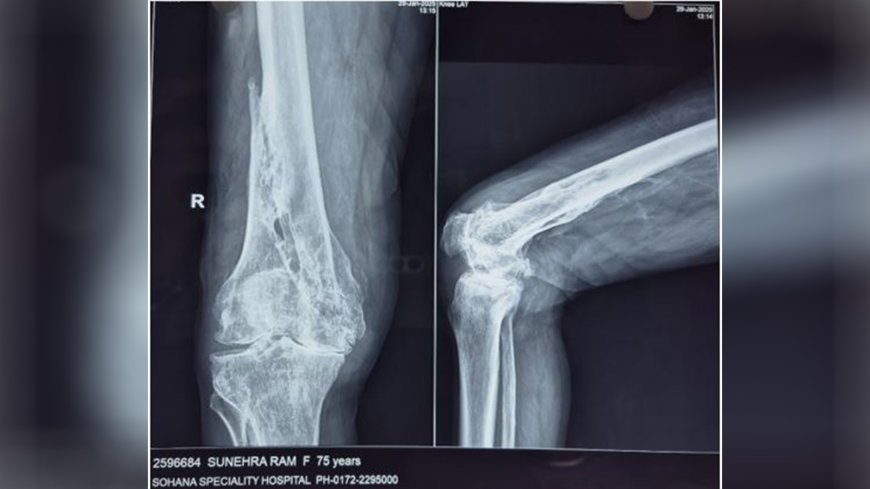

The case involved a 75-year-old male patient suffering from severe post-traumatic arthritis due to an old malunited fracture of the right distal femur. The complexity of the case was compounded by significant cardiac comorbidities, including a low ejection fraction (30%), making conventional total knee replacement (TKR) infeasible. Before meeting Dr. Sachdeva, the patient had been refused at multiple centres due to the high perioperative risk and the need for specialized robotic and navigation-assisted expertise.

Despite these challenges, Dr. Gagandeep Sachdeva and his skilled team took on the case with meticulous planning and precision. Preoperative CT imaging and comprehensive cardiac and anaesthesia evaluations paved the way for a personalized surgical approach. The fully automated joint replacement robotic assistance was instrumental in ensuring accurate gap balancing and tracking, which is crucial for achieving optimal surgical outcomes in this complex scenario.